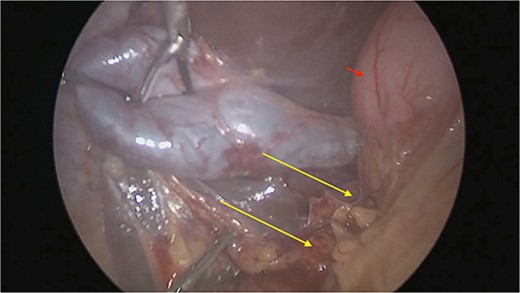

There were extensive perihepatic adhesions with involvement of the subhepatic space (Fig. 3). The initial intraoperative assessment was that this inflammation was secondary to a prior cholecystitis, but subsequent dissection revealed a pristine gallbladder (Fig. 4) with inflammatory adhesions in the pyloro-duodenal region (Fig. 5). All adhesions encasing the duodenum were lysed and the duodenum was kockerized (Fig. 6).

Extensive supra- and subhepatic adhesions were noted at laparoscopy.

The gallbladder was dissected free of the dense adhesions. There was no evidence of previous cholecystitis. The stomach (short arrow) was spared of adhesions, but the first and second parts of the duodenum were encased (long arrows).